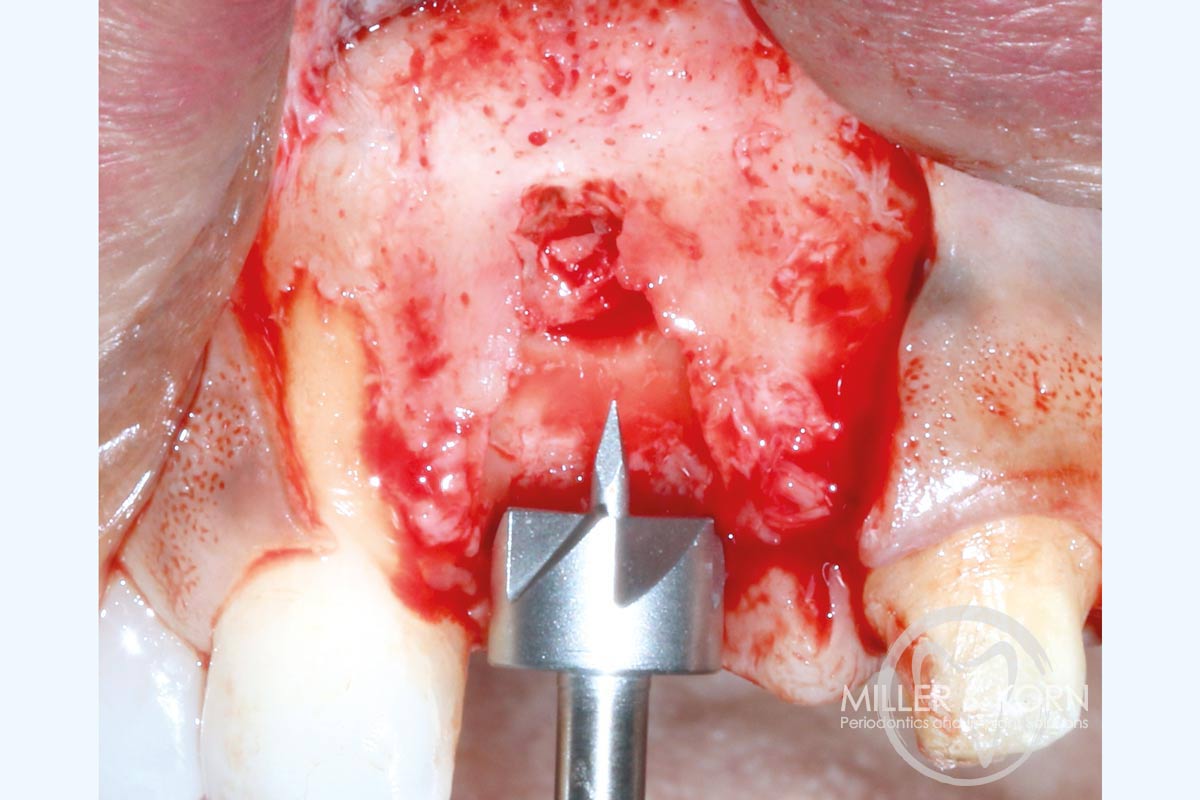

6/22 - Trephine drilling to prepare the site for the allograft ring.Immediate implant placement and regeneration of ridge using an allograft bone ring and Jason® membrane - Drs. Miller and Korn